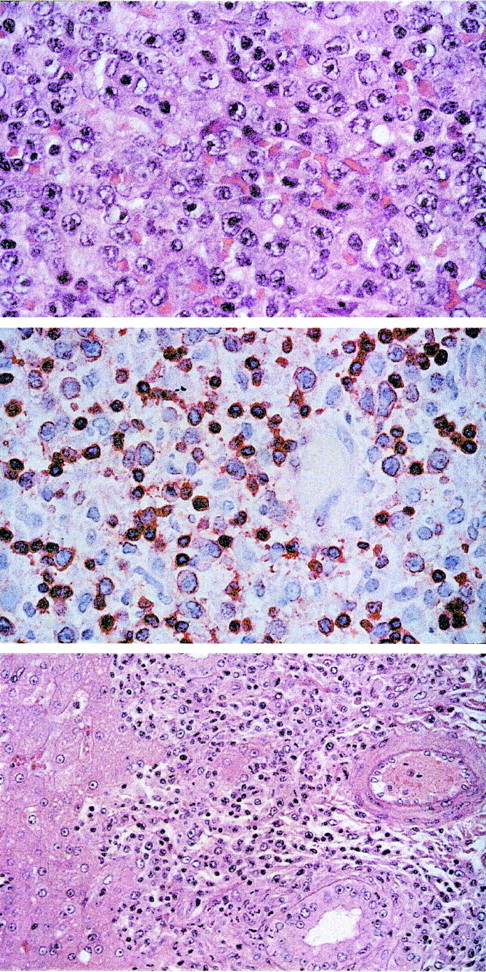

In contrast, the naive control animals died from lymphoma at day 13 or 14 after high-dose infection. Lymphoma cell lines were established ex vivo from both animals, and the virus was easily reisolated from PBMCs. Foamy virus reactivation terminated the cultures from 1 animal after several weeks. T cell lines in the other animal were phenotypically indistinguishable from in vitro transformed T cells. Necropsy samples of lymph nodes, thymus, spleen, bone marrow, kidney, and brain of these animals contained large amounts of virus DNA (data not shown). Whereas IFN-γ, IL-6, and TNF-α were not detectable in plasma samples after autologous transfusions, IFN-γ (up to 225.1 pg/mL) and IL-6 (up to 10.2 pg/mL) were increased in plasma samples from the terminally ill animals Mf406 and Mf409. Histopathological and immunohistochemical analysis showed widespread infiltrates of a pleomorphic peripheral T-cell lymphoma consisting of medium-sized and large blasts with vesicular nuclei and prominent nucleoli (Figure3, upper panel). The blasts were positive for the T-cell marker CD3 (Figure 3, central panel) but negative for CD20. The infiltrates of blasts involved the lymph nodes, spleen, Waldeyer's ring, intestine, and pancreas of animal Mf406, and they were detected in lymph nodes, spleen, intestine, kidney, salivary glands, lung, and liver (Figure 3, lower panel) of animal Mf409. The lymph nodes were enlarged in both animals and showed a widening of sinuses and T zones by the infiltrating blasts as well as a loss of follicular structure.

T-cell lymphoma after intravenous infection with herpesvirus saimiri C488 of naive cynomolgus monkeys.

The tissue sections were stained with hematoxilin/eosin. Upper panel: Lymph node showing peripheral pleomorphic T-cell lymphoma with medium-sized and large blasts containing vesicular nuclei and prominent nucleoli (original magnification ×100). Central panel: Immunostaining of the medium-sized and large blasts and some accompanying small lymphocytes for CD3 (original magnification ×63). Lower panel: Infiltration of the portal tracts of the liver by the blast cells (original magnification ×40).